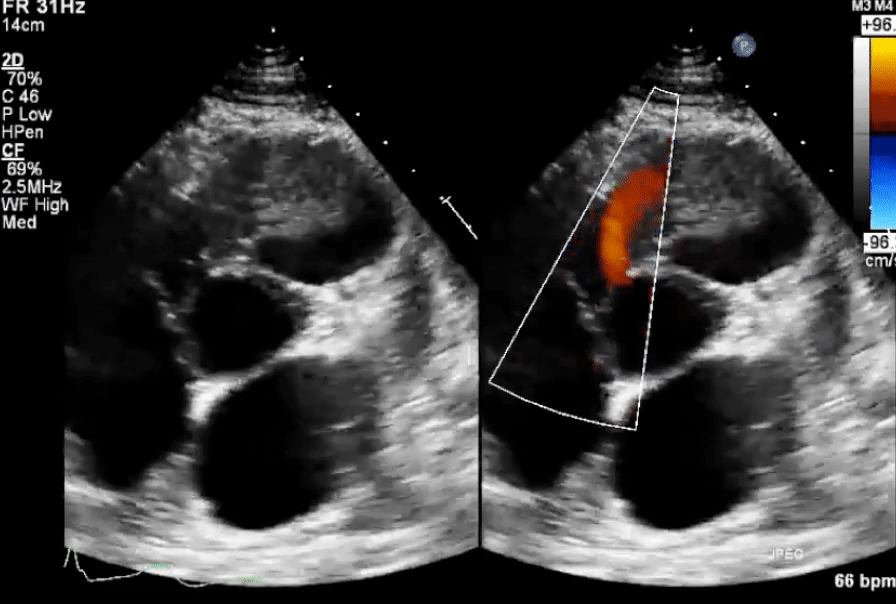

Echo in VSD

-1754871370645.webp)

-

Membranous VSD

Inlet VSD